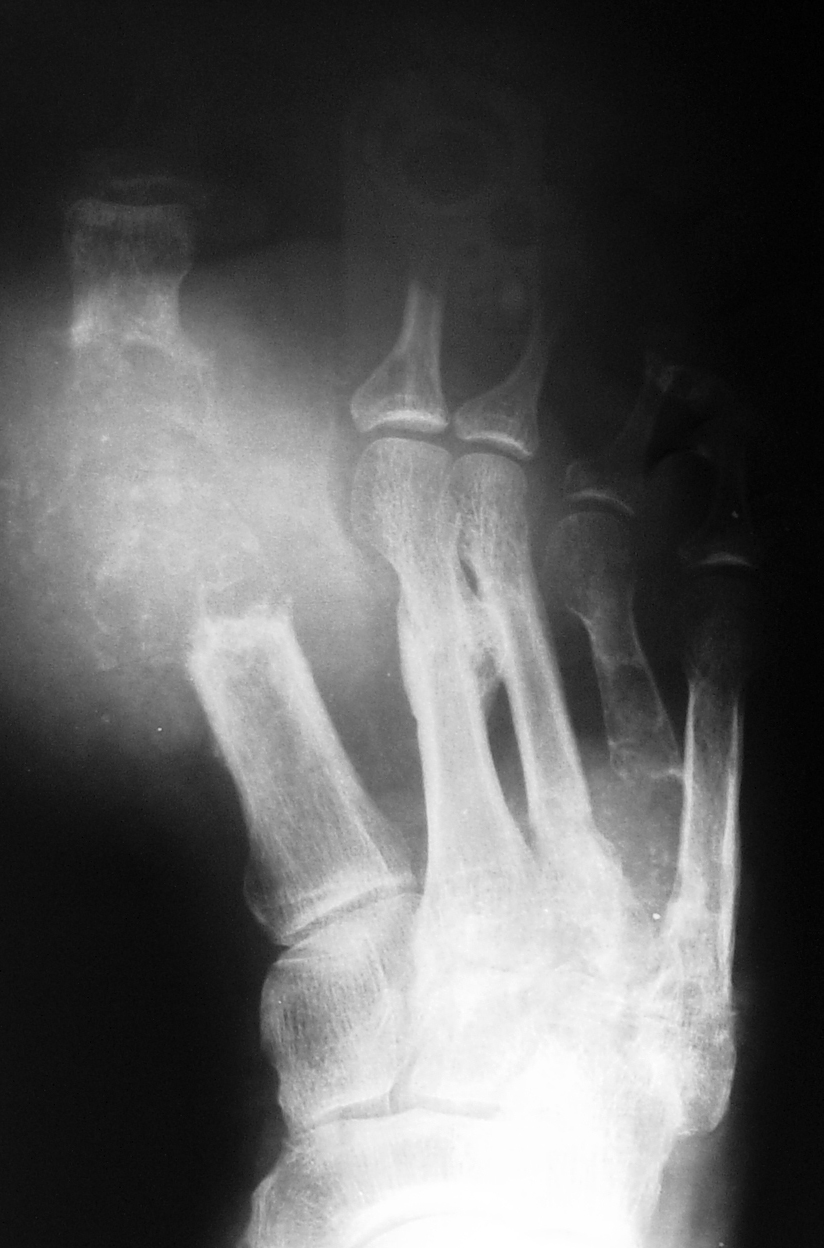

O exame de raio x serve para visualizar os efeitos da degeneração e o grau de acometimento da articulação inflamada.

RX - Destruição Articular pela Artrite Gotosa